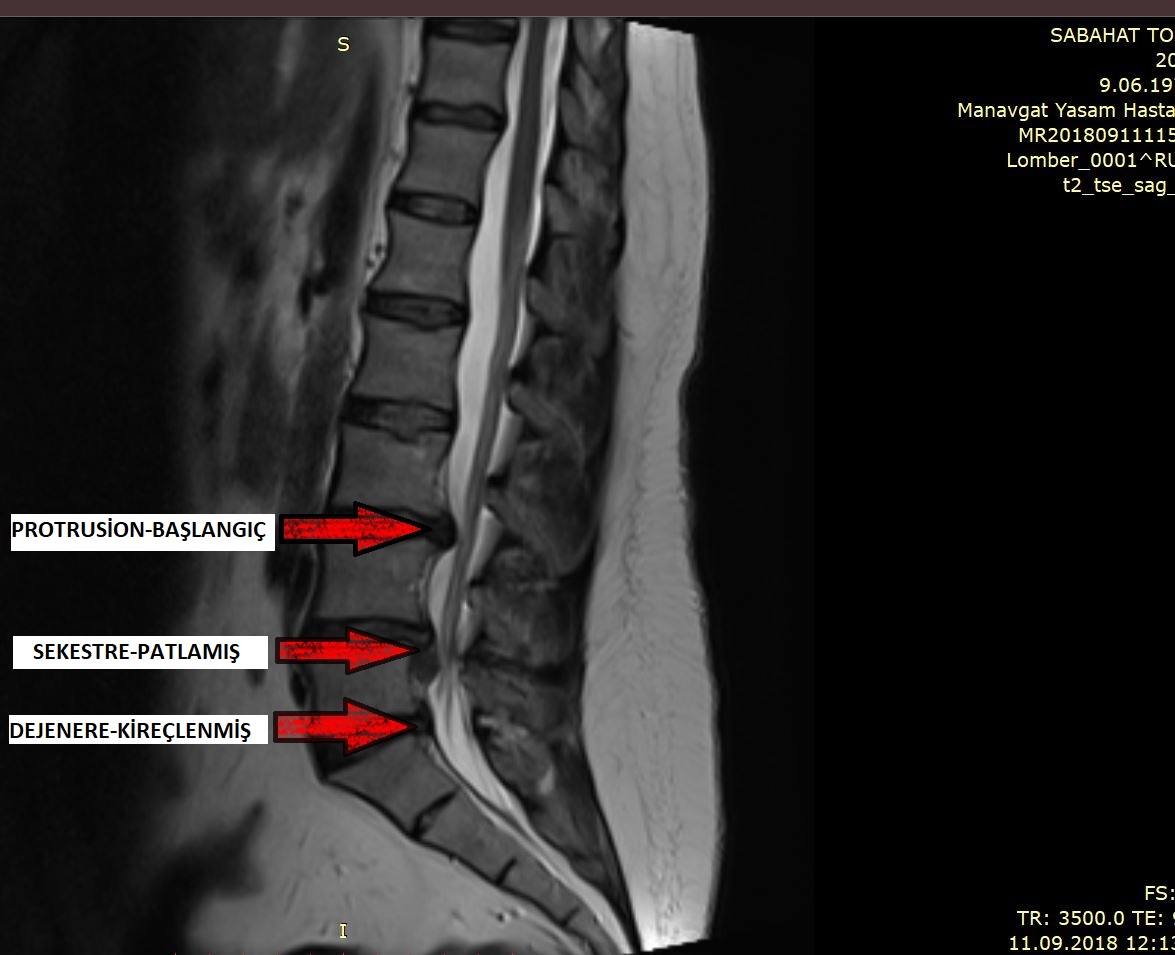

Bel Fıtığı Nedir?

Bel Fıtığı

Genelde 30 ile 60 yaş arasındaki kişilerde sık görülmesine rağmen, hemen her yaşta ortaya çıkabilen…